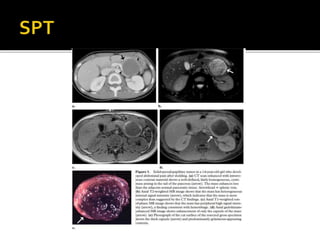

 Características

morfológicas:

 Grande x: 9 cm.

 Crecimiento lento.

 Masa bien encapsulada.

 Cola > cabeza.

 Desplaza más que invade,

raro obstrucción biliar

 Hipodenso enTC, baja

señal enT1 yT2.

 Hemorragia interna y

degeneración quística

 Hemorragia hiper-aguda:

hiperintensa enT1 con intensidad

de señal variable enT2.

 Hemorragia crónica: hipointensa

en ambas secuencias.

 Nivel fluido-fluido/ fluido –debris:

10-18% por efecto del

hematocrito.

 Calcificaciones periféricas 30%.

 Realce heterogéneo periférico

durante la fase arterial y realce no

uniforme periférico pero

agresivo. (realce menor que el

páncreas)